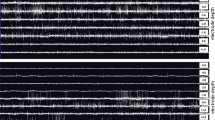

Electrode Accuracy

Deviation from the intended target is measured when looking down the view of the planned trajectory on the verification CT for a given side (Fig. 5). The electrode placement accuracy is the radial distance between the center of the implanted electrode and the center of the target location (Fig. 6). Errors in depth of the cannula after implantation were also calculated and reported, however, this study focuses primarily on radial errors as errors related to the depth of the cannula measured by the verification CT were subsequently corrected by using the micro-drive system to adjust the depth placement to eliminate this depth error. Unless otherwise stated, the errors reported in this study refer to radial errors. An algorithm was developed in MATLAB 2017b (The Mathworks, Inc., Natick, MA) to automate the electrode placement accuracy measurement process. It utilizes image processing tools to locate the center of the electrode and target. It then quantifies and converts the accuracy to standard units of mm. The development of the automated measurement process eliminates human variance in measurement and bias. A comparison of 27 patients with 53 electrodes implanted measured both manually and using the algorithm shows a statistically significant difference (p = 0.008) between the final placement accuracies of 0.79 ± 0.36 and 0.85 ± 0.35 mm for the manual and automatic measurement systems, respectively. The automated process also saves computational time, which is beneficial when analyzing large cohorts.

Overlay of the preoperative MRI with target trajectory (blue) and verification CT cannula placement (red). Close-up with 5.0 mm reference scale bar shown on the right—this image was used to measure the difference between center of the target site and the center of the implanted cannula. Images are shown looking along the target cannula trajectory.